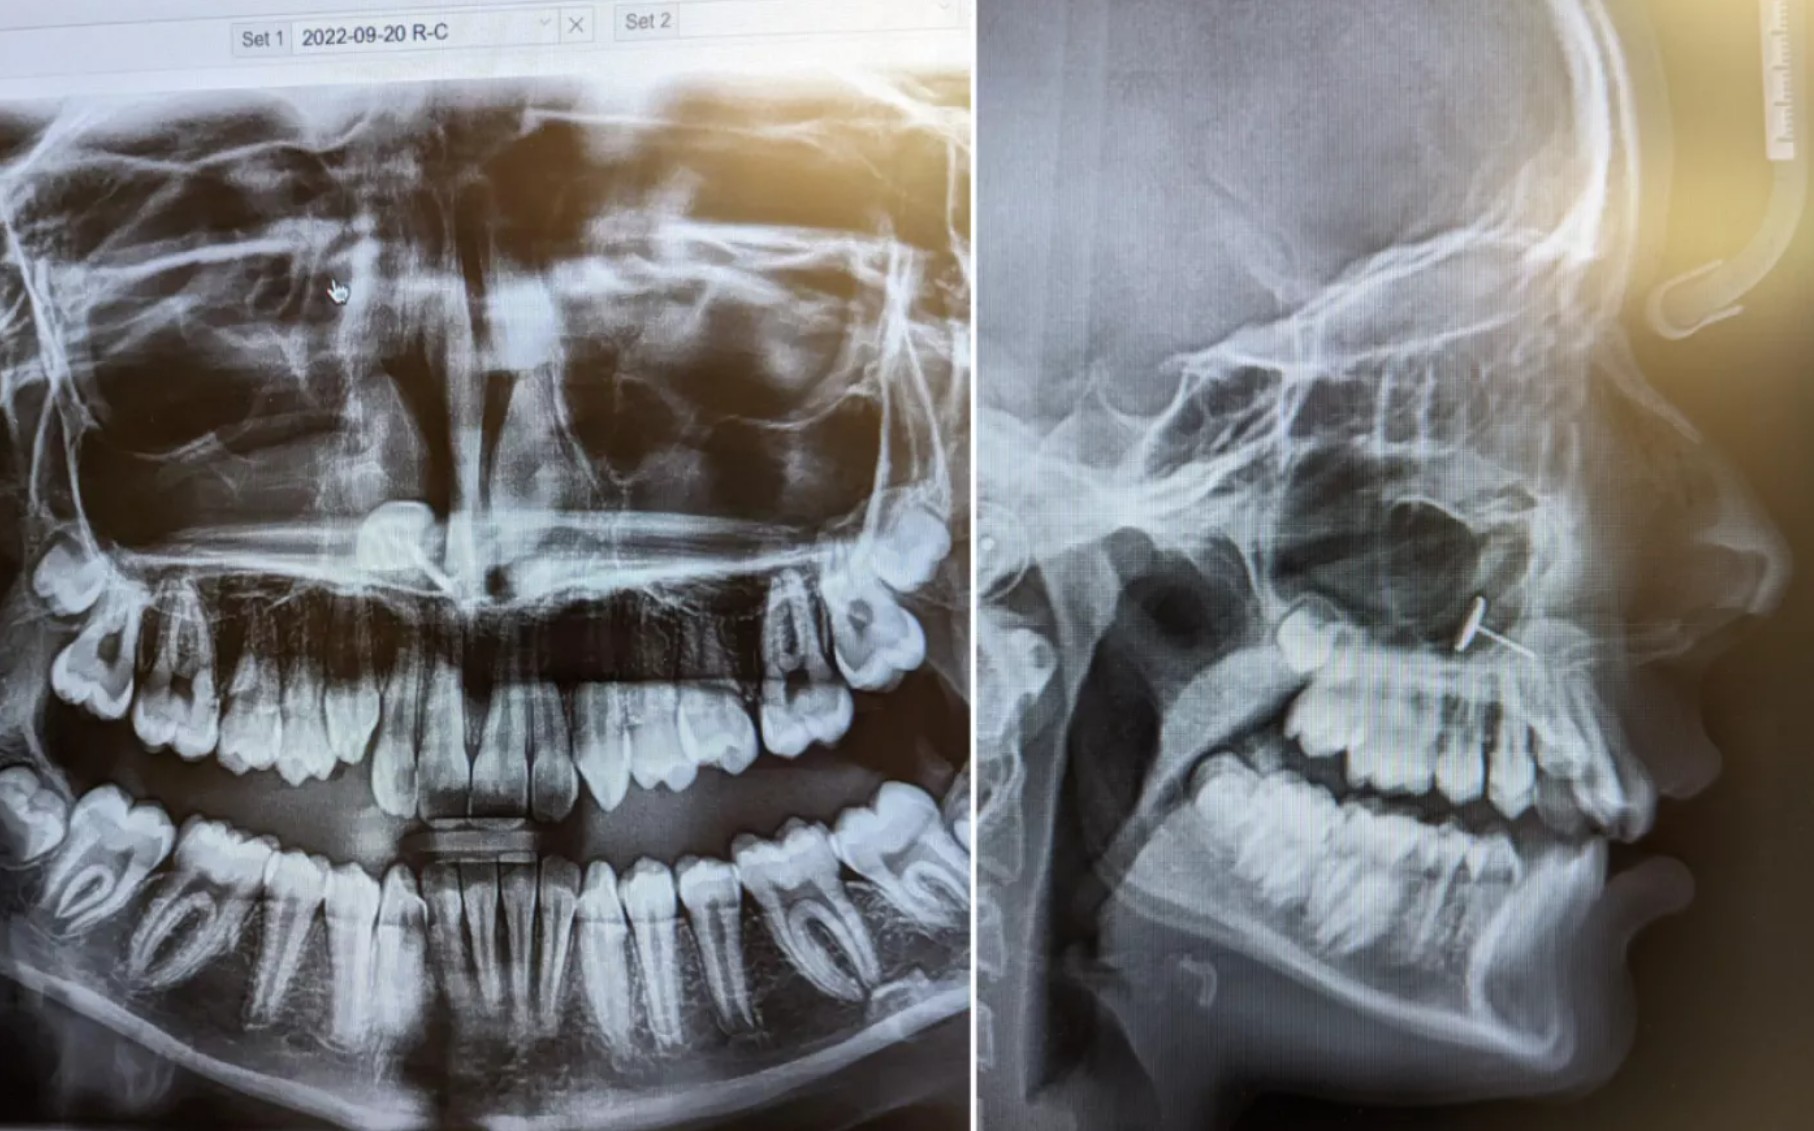

"Ortodont je prišel v sobo in na zaslonu pokazal rentgenske slike," je mati povedala za Newsweek. "Vsi smo jih zagledali hkrati in nekaj minut poskušali ugotoviti, kaj sploh gledamo," je dejala.

Na sliki je bilo videti majhen kovinski predmet, ujet v hčerinih sinusih. Mati ni imela pojma, kako bi lahko tja zašel, a ena oseba v prostoru je točno vedela, kaj se je zgodilo: njena hči.

"Vzela je uhan, s katerim so ji prebodli ušesa, in ga poskušala potisniti skozi nos," je pojasnila mati. "Očitno je v nekem trenutku poskusila potisniti uhan skozi nos od znotraj," je povedala mati najstnice. "Ne vem, ali je kihnila, ampak na koncu je uhan vdihnila. Zataknil se je v njenih sinusih."

"Ko smo ugotovili, kaj je in kako je tja prišlo, sem poklicala specialista za ušesa, nos in grlo, ki ji je pred leti odstranil mandlje, in z zelo dolgimi medicinskimi pincetami ter mirno roko je predmet odstranil. Hči med postopkom ni čutila bolečine in glede na okoliščine je vse skupaj kar dobro prenesla," je za Newsweek sklenila pomirjena mati.